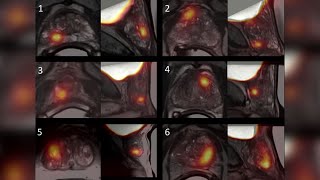

Imaging’s Role in the Detection, Diagnosis and Treatment of Prostate Cancer Prostate Cancer Imaging

Prostate Cancer Imaging Five Uses for MRI In Prostate Cancer | Prostate Cancer Staging Guide

Imaging’s Role in the Detection, Diagnosis and Treatment of Prostate Cancer Prostate Cancer Imaging

Prostate Cancer Imaging Five Uses for MRI In Prostate Cancer | Prostate Cancer Staging Guide